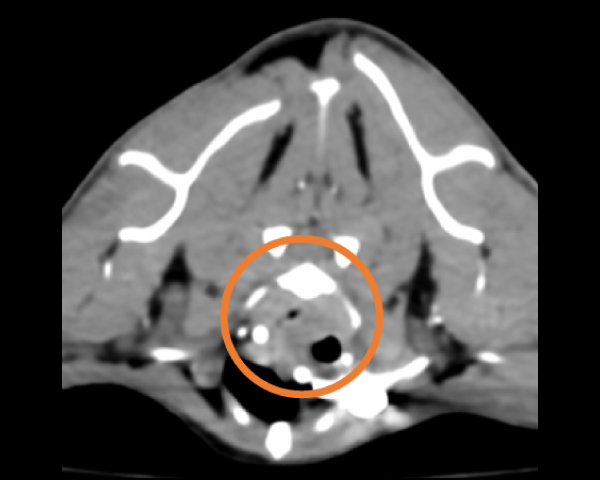

CT検査にて気管の圧迫を確認